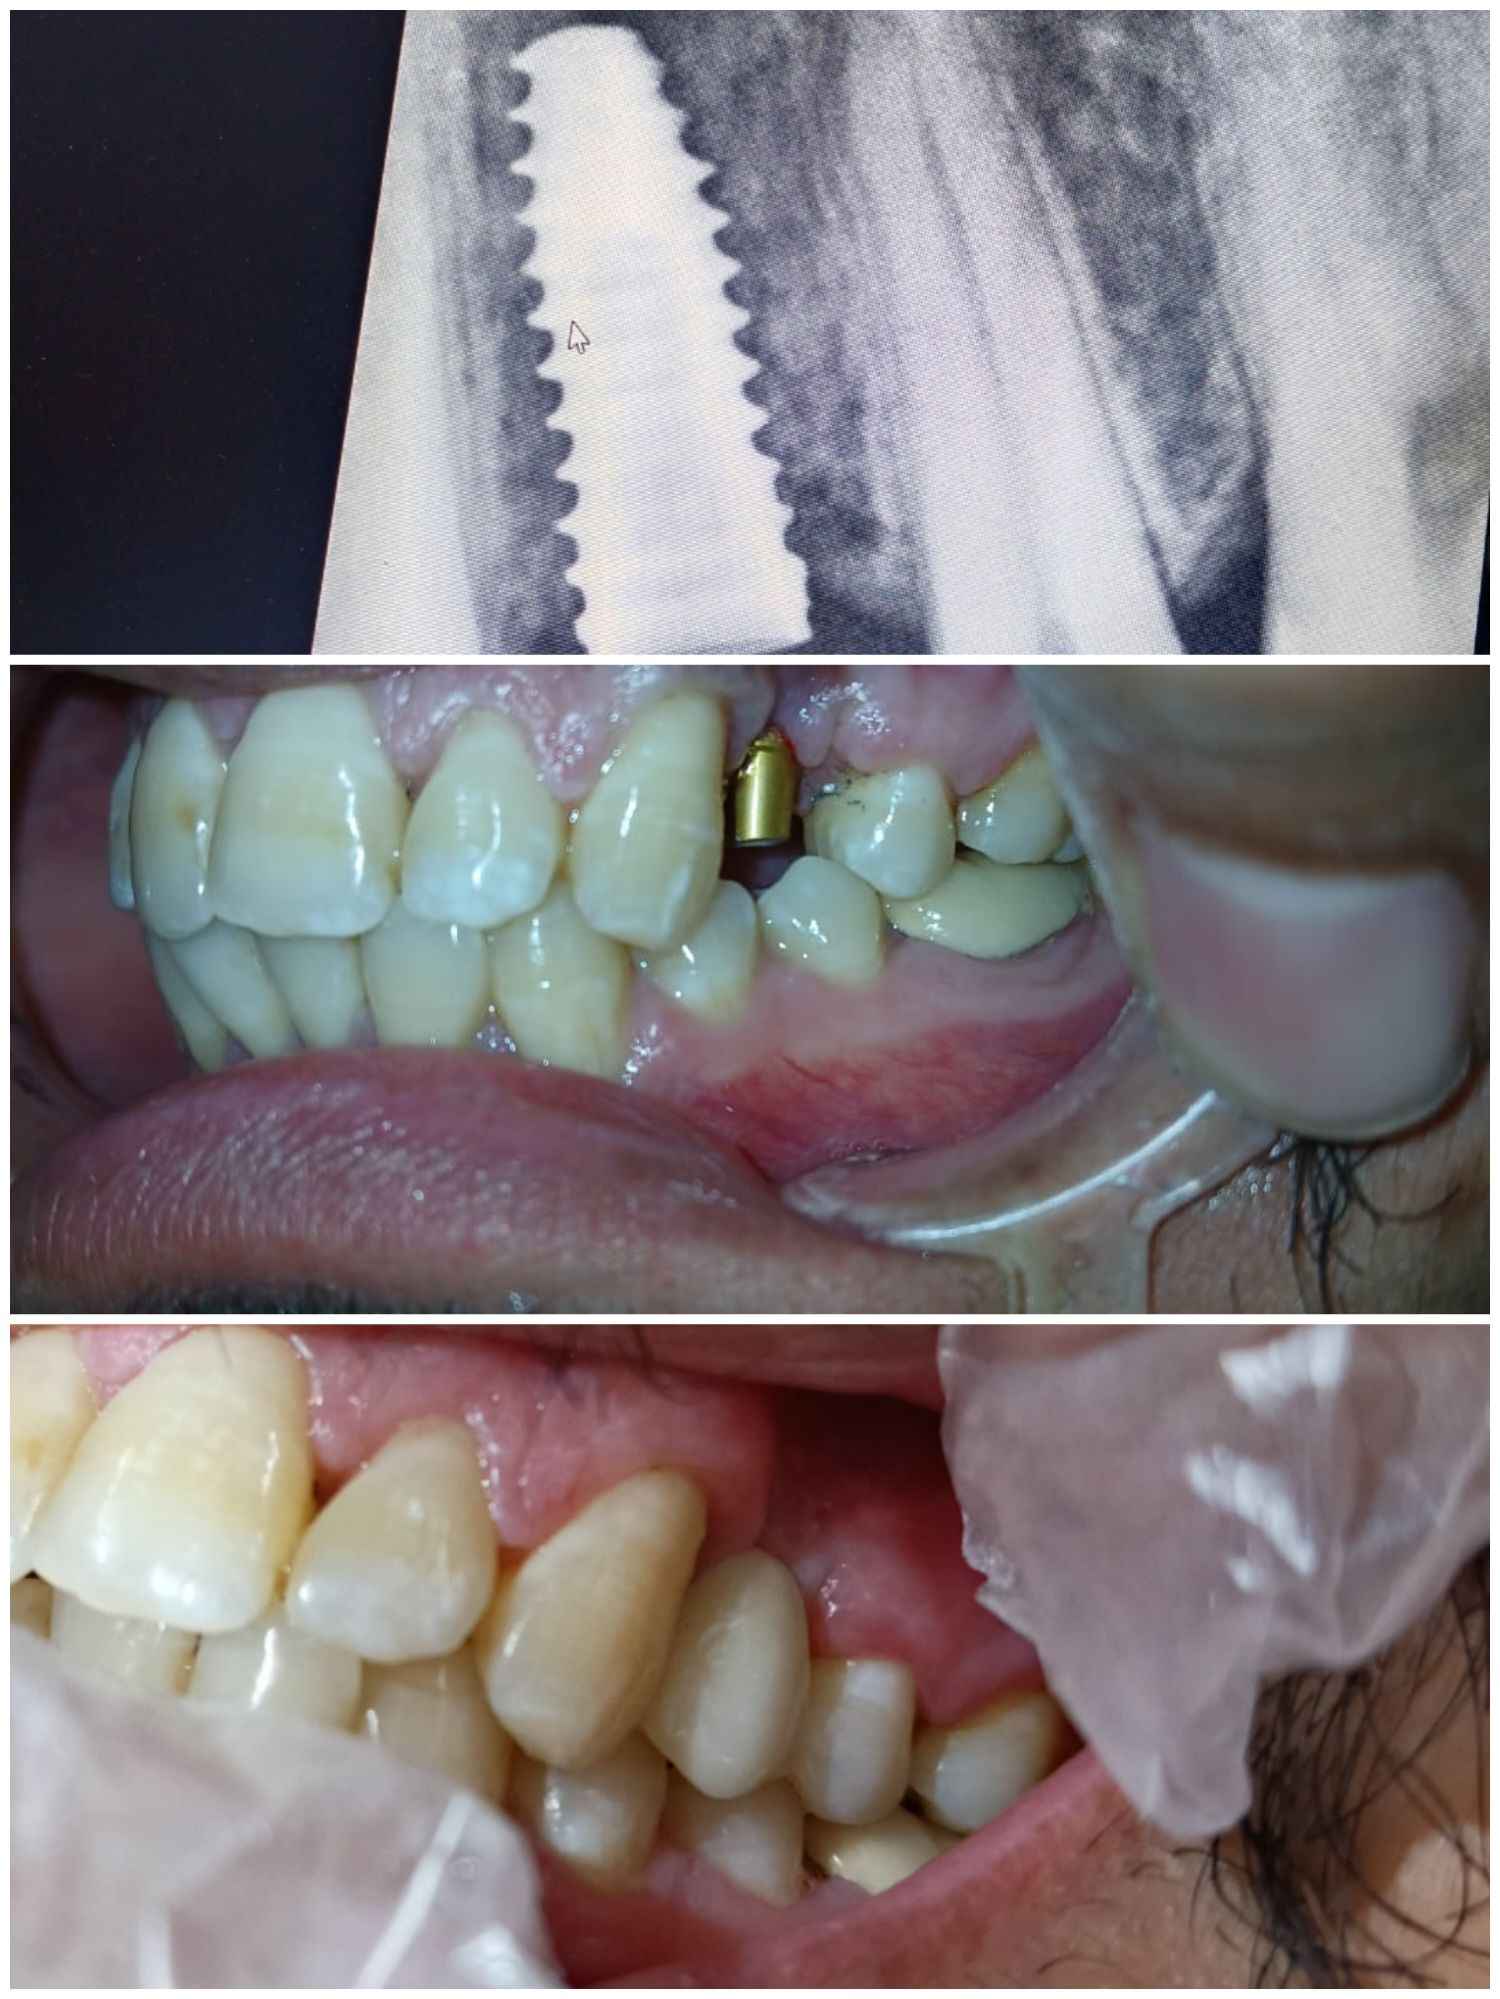

Advanced Portable Dental X-ray for minimum radiation exposure. High-precision imaging for accurate diagnosis.